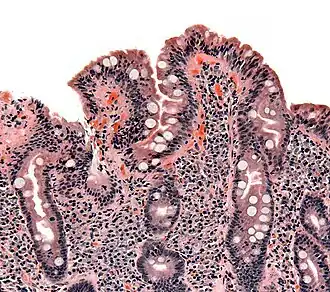

Biópsia do intestino delgado onde a doença celíaca se manifesta por deformações nas vilosidades, hiperplasia e infiltração de linfócitos nas criptas.

A doença celíaca é causada por uma reação do organismo ao glúten, um conjunto de proteínas presentes no trigo e em outros cereais como a cevada ou centeio.[9][18][19] A aveia em quantidades moderadas é geralmente tolerada, dependendo da variedade[18][20] e desde que não esteja contaminada com outros cereais com glúten.[18][21] Ao ser exposto ao glúten, o sistema imunitário desencadeia uma resposta anormal, produzindo uma série de anticorpos que podem afetar diversos órgãos.[4][22] No intestino delgado, esta resposta imunitária provoca uma reação inflamatória que faz diminuir as vilosidades intestinais.[10][11] Isto afeta a absorção de nutrientes pelo intestino, o que em muitos casos causa anemia.[10][19]